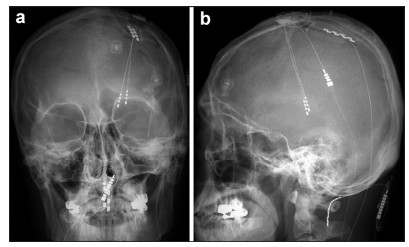

After a burr hole and dural opening were made, microelectrode recording and stimulation were used to map the Vc targets (Figure 1b). The activity of the individual firing units and their receptive fields (RF), defined as the body sites where tactile stimulation or movement evoked changes in the electrical firing patterns, was recorded along the planned trajectories (mostly three or four trajectories in one session) (Figure 1c). Based on the RF mapping, a DBS electrode (Medtronic model 3387, Medtronic Inc., Minneapolis, MN) was implanted in the target. Macrostimulation was conducted through the DBS leads to verify stimulation-induced paresthesia coverage of the painful area and any adverse effects of the macrostimulation. After the absence of an adverse neurologic deficit was confirmed with DBS, general intravenous anesthesia was administered. An inverted U-shaped scalp incision was made just behind the frontal incision for the DBS, and an approximately 5-cm sized craniotomy was performed along the course of the precentral gyrus and the central sulcus (CS)[6-20] (Figure 1d). The CS was localized with the aid of phase-reversal of the somatosensory evoked potential and evoked EMG response of the muscle (Figure 1e). After the location and course of the CS were confirmed, a paddle electrode (Lamitrode 44®, St. Jude Medical, Plano, Texas, or Resume® TL, model 3986A, Medtronic Inc., Minneapolis, MN) was placed in the epidural space (Figure 1f). Further, the distal ends of the paddle and DBS electrodes were connected to a percutaneous extension cable through the subcutaneous tunnel (Figure 2).

| Figure 2 Anterior-posterior a and lateral b projections of skull x-ray films of a patient (#10) who underwent a simultaneous DBS/ MCS trial for intractable, chronic neuropathic pain. This patient had both thalamic Vc and internal capsule DBS electrodes combined with a left-side MCS electrode. Note the previously implanted C1–C2 paddle lead for treatment-resistant complex regional pain syndrome with whole-body involvement, which was more severe in the right hemibody. In this particular patient, we obtained >50% pain relief with the initial MCS trial. However, thalamic Vc stimulation aggravated the hemibody pain. The prominent analgesic effect of MCS faded postoperatively within six months. However, the patient still today (24 months after MCS) uses chronic MCS for unremitting pain. He judged MCS as being much more effective than spinal cord stimulation. |